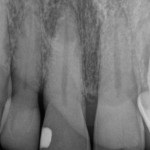

Periapical Image of Tooth #11

These teeth tested normal to percussion, palpation, probing, and mobility and were normal to thermal challenge. Radiographically, there appeared to be a periapical radiolucency at the apex of tooth #11 and some early coronal calcification of the pulp chamber. The contradictory signs of periapical radiolucency and normal response to thermal challenge prompted this astute dentist to refer the patient for further evaluation to our office.

Radiographic imaging consisted of periapical images and a small volume CBCT. The periapical image, seen above, did appear to have a periapical radiolucency. There was also calcification and pulpal recession in the upper part of the pulp chamber, the likely cause of the mild tooth darkening, something often seen with trauma and pulpal death.